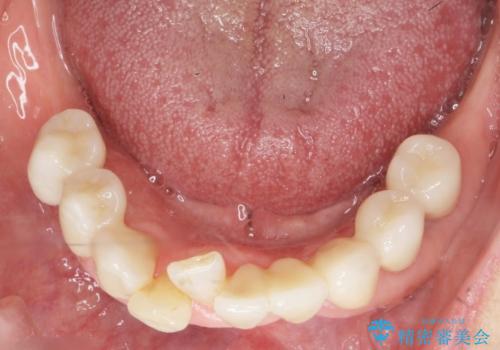

気にされていた前歯と奥歯の動揺がなくなったことと自然な仕上がりに喜んで頂けました。

クラウンの種類:オールセラミッククラウン スタンダード

入れ歯も抵抗があるとのことから、相談を重ね、今の状態では保存不可能な下の前歯(左下2)を抜去し、ブリッジや連結補綴により動揺を抑えることにしました。

また、咬み合わせが反対になっている上の前歯(左上2)も補綴で形を変えることにより、咬合を改善しました。